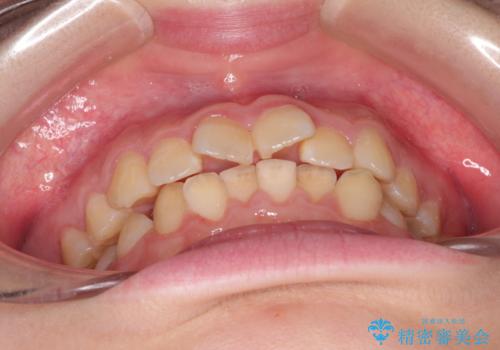

なるべく通院回数を減らして矯正したい インビザラインでのガタガタ矯正

- 上下の歯並びを治したいとのことで来院されました。

受験生ということもあり、なるべく通院回数を減らしての矯正を希望されたので、インビザラインで治療をすることにしました。